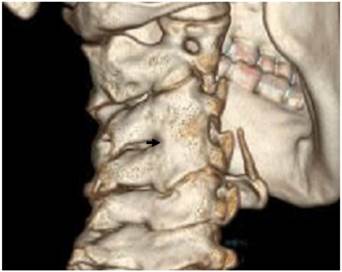

Reformatted CT scan of the cervical spine in a 13-year-old girl showed anterolateral ossification of the anterior longitudinal spinal ligament (Forestier -like disease) with subsequent development of fusion-like abnormality (fig 1).

Reformatted CT scan of the cervical spine in a 13-year-old girl showed anterolateral ossification of the anterior longitudinal spinal (Forestier disease) (arrow).